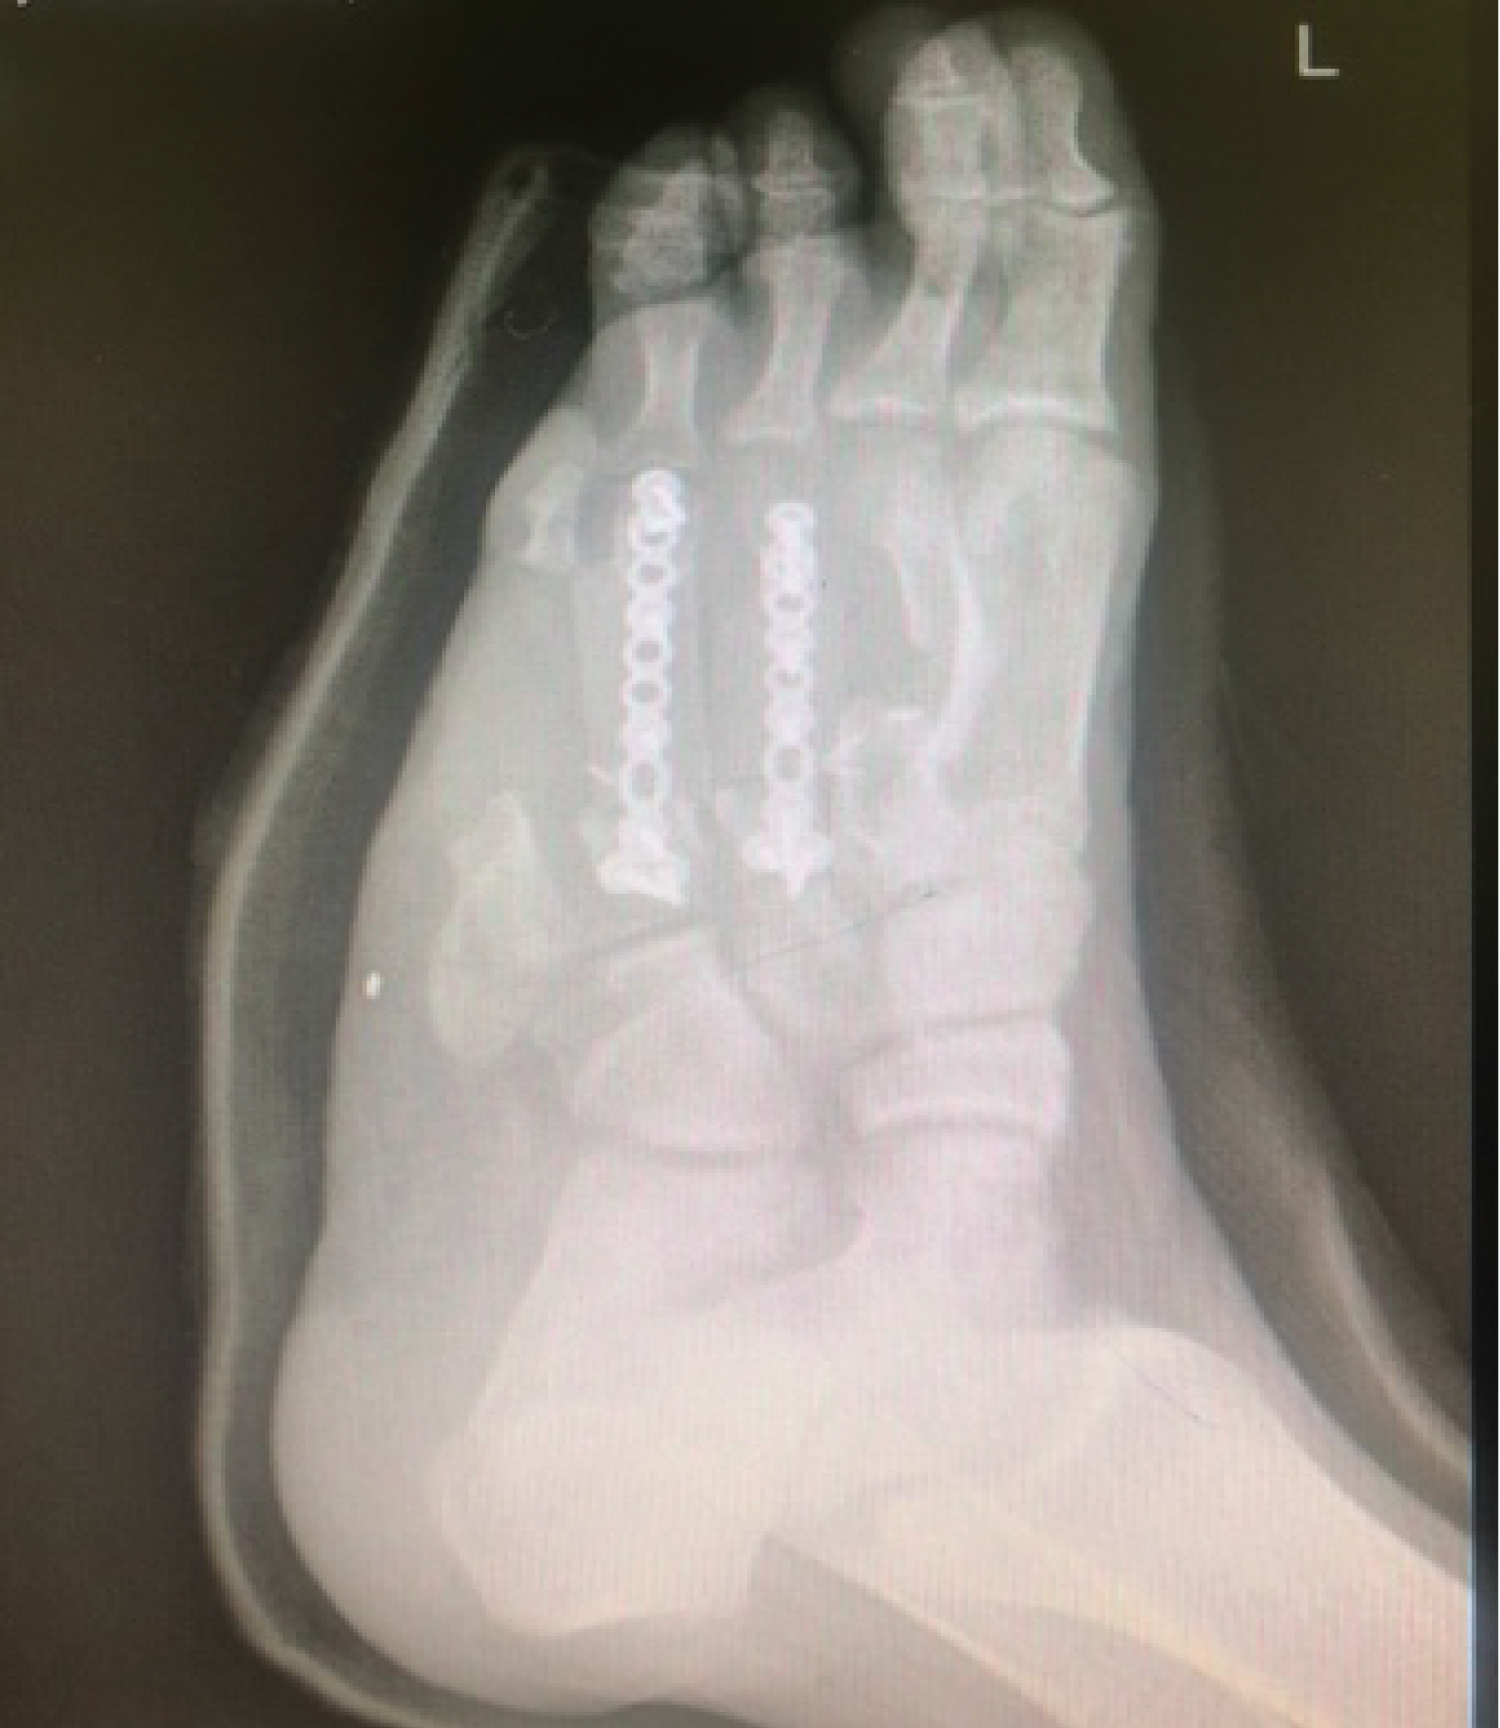

A good approximation of the metatarsal head cascade was demonstrated radiographically. We used the Arthrex® foot plating system to secure the bone graft with locking screws into the metatarsal head, metatarsal base and screws to secure the graft onto the plate (Figure 6). Stable fixation was confirmed by clinical examination on the operating table and with intraoperative fluoroscopic pictures. The wound was thoroughly irrigated and the flap was closed with interrupted non-absorbable sutures.

Figure 6: Intra-operative picture of graft fixation. View Figure 6

His flap healed uneventfully within 2 weeks and his radiographs were satisfactory (Figure 7 and Figure 8). He was comfortable enough to partially weight bear in a full cast avoiding any forefoot loading at that stage.

Figure 8: radiograph at 2 weeks. View Figure 8